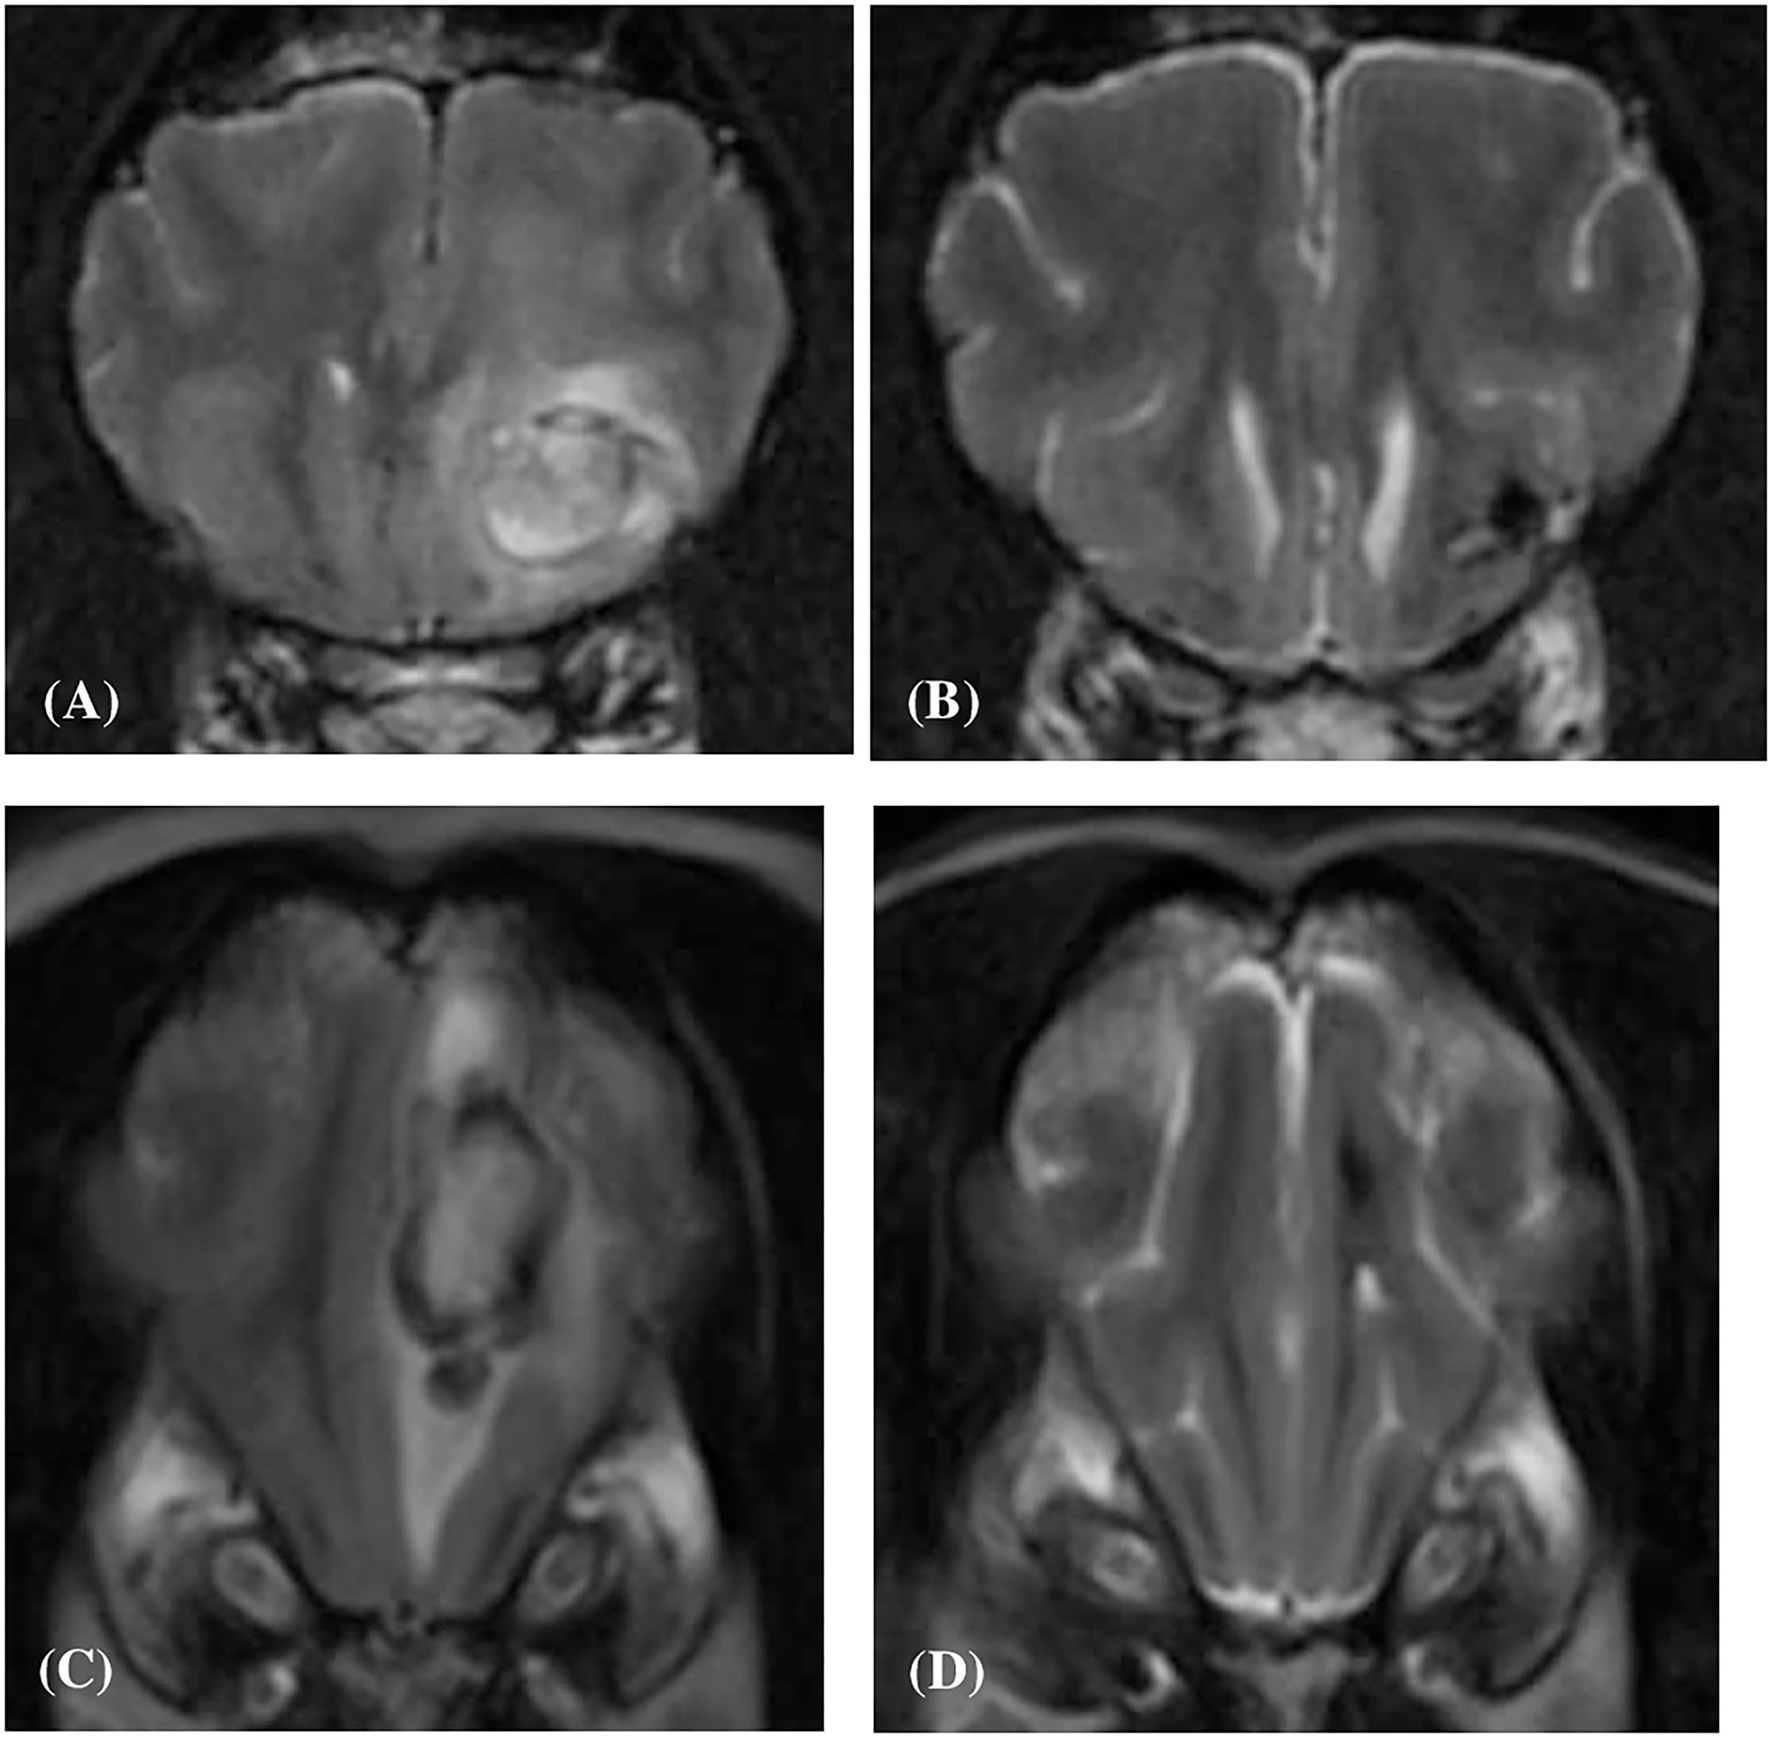

Figure 6

Transverse T2-weighted image (A) of a dog (Case 10) with an intracranial intra-axial hematoma affecting white matter of the left frontal lobe at first presentation. Transverse T2-weighted image (B) of the same dog as displayed in (A) at the same location but 83 days later. Transverse T2-weighted image (C) of a dog (Case 2) with an intracranial intra-axial hematoma affecting the white matter of the left frontal lobe (centrum semiovale) at first presentation. Transverse T2-weighted image (D) of the same dog as displayed in (C) at the same location but 207 days later. In both the follow up images (B,D) the lesions have reduced dramatically in volume, are uniformly hypointense and perilesional oedema has resolved. This is illustrative of normal intra-axial intracranial hematoma contraction and maturation.

Four out of the ten dogs had repeat MRI studies; case 2, case 4, case 8 and case 10 at 207, 32, 46, and 83 days following their initial MRI study, respectively (median value; 64.5 days). On evaluation of these follow-up studies, it was observed that in all four cases the lesions had markedly reduced in volume, were hypointense in all sequences, and both perilesional edema and contrast enhancement were absent (Figure 6).